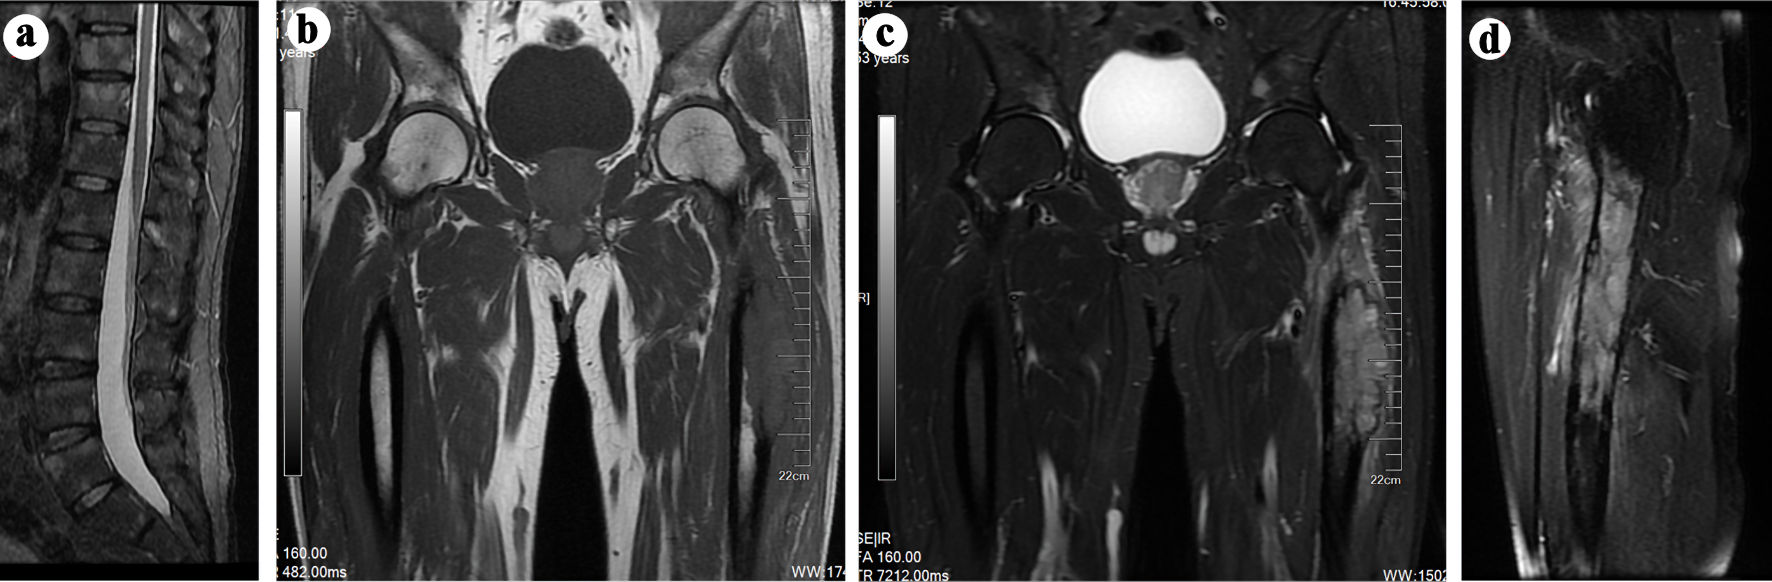

Then we arranged a magnetic resonance imaging (MRI) to examine the thigh, hip joint, and the spine. The results of thigh and hip joint revealed aggressive cortical destruction of left proximal femur, with an adjacent extraosseous soft tissue mass. MRI results also showed possible multiple bone metastases to the right proximal femur, bilateral ilium, bilateral ischium, bilateral pubis, and spine (Fig. 1a-d). Accidentally, the patient develops spontaneous fracture of left proximal femur, which could not enable a computed tomography (CT) scan due to unbearable pain. Therefore, an ultrasound-guided needle biopsy of the mass was conducted, and lung adenocarcinoma was diagnosed based on pathologic examination. In order to facilitate further examination and treatment, we applied external fixation to temporarily fix the displaced pathological fracture. Then, we conducted chest CT, with results showing a lesion at the left upper lobe (Fig. 2a, b), which is finally revealed as stage IV adenocarcinoma (Fig. 3a-c). Then the patient was transferred to the oncology department for further management, where mutational analysis of the tumor revealed an EGFR exon 19 deletions mutation, and the patient then received osimertinib, an EGFR-tyrosine kinase inhibitor (TKI).

![]() Click for large image | Figure 1. (a-c) MRI scans indicating potential multiple metastatic lesions in bilateral proximal femur, ilium, ischium, pubis, and spine. (b) T1-weighted sagittal spin-echo sequence of the thigh and hip joint displaying a hypointense lesion in the left proximal femur. (c, d) T2-weighted sagittal spin-echo sequence with fat-suppression demonstrating a hyperintense lesion involving intraosseous and extraosseous soft tissue in the left proximal femur. MRI: magnetic resonance imaging. |